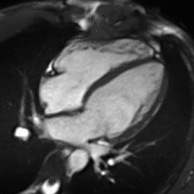

عملکرد قلب با استفاده از تصویربرداری ساین

اطلاعات عملکردی و ساختاری با استفاده از توالی ساین bSSFP بدست میآید. اینها معمولاً به صورت گذشته نگر و دارای کانتراست بسیار بالایی در تصویربرداری قلبی به دلیل نسبت نسبتاً زیاد T2: T1 خون در مقایسه با میوکارد هستند. تصاویر معمولاً برای دستیابی به طرحهای استاندارد قلبی که برای ارزیابی مورد استفاده قرار میگیرند، به صورت پی در پی برنامهریزی شدهاند. جریان پر تلاطم باعث برهم خوردن فاز میشود و از دست دادن سیگنال به بیماری دریچه ای اجازه قدردانی کیفی میدهد. ساینهای محور کوتاه بطن چپ از پایه به سمت حداکثر حفره بدست میآیند و برای کمی کردن حجمهای پایان دیاستولیک و سیستولیک انتهایی، و همچنین توده میوکارد استفاده میشود. توالی برچسب زدن الگوی شبکه که با انقباض قلبی تغییر شکل میدهد را تحریک میکند و باعث کرنش میشود.